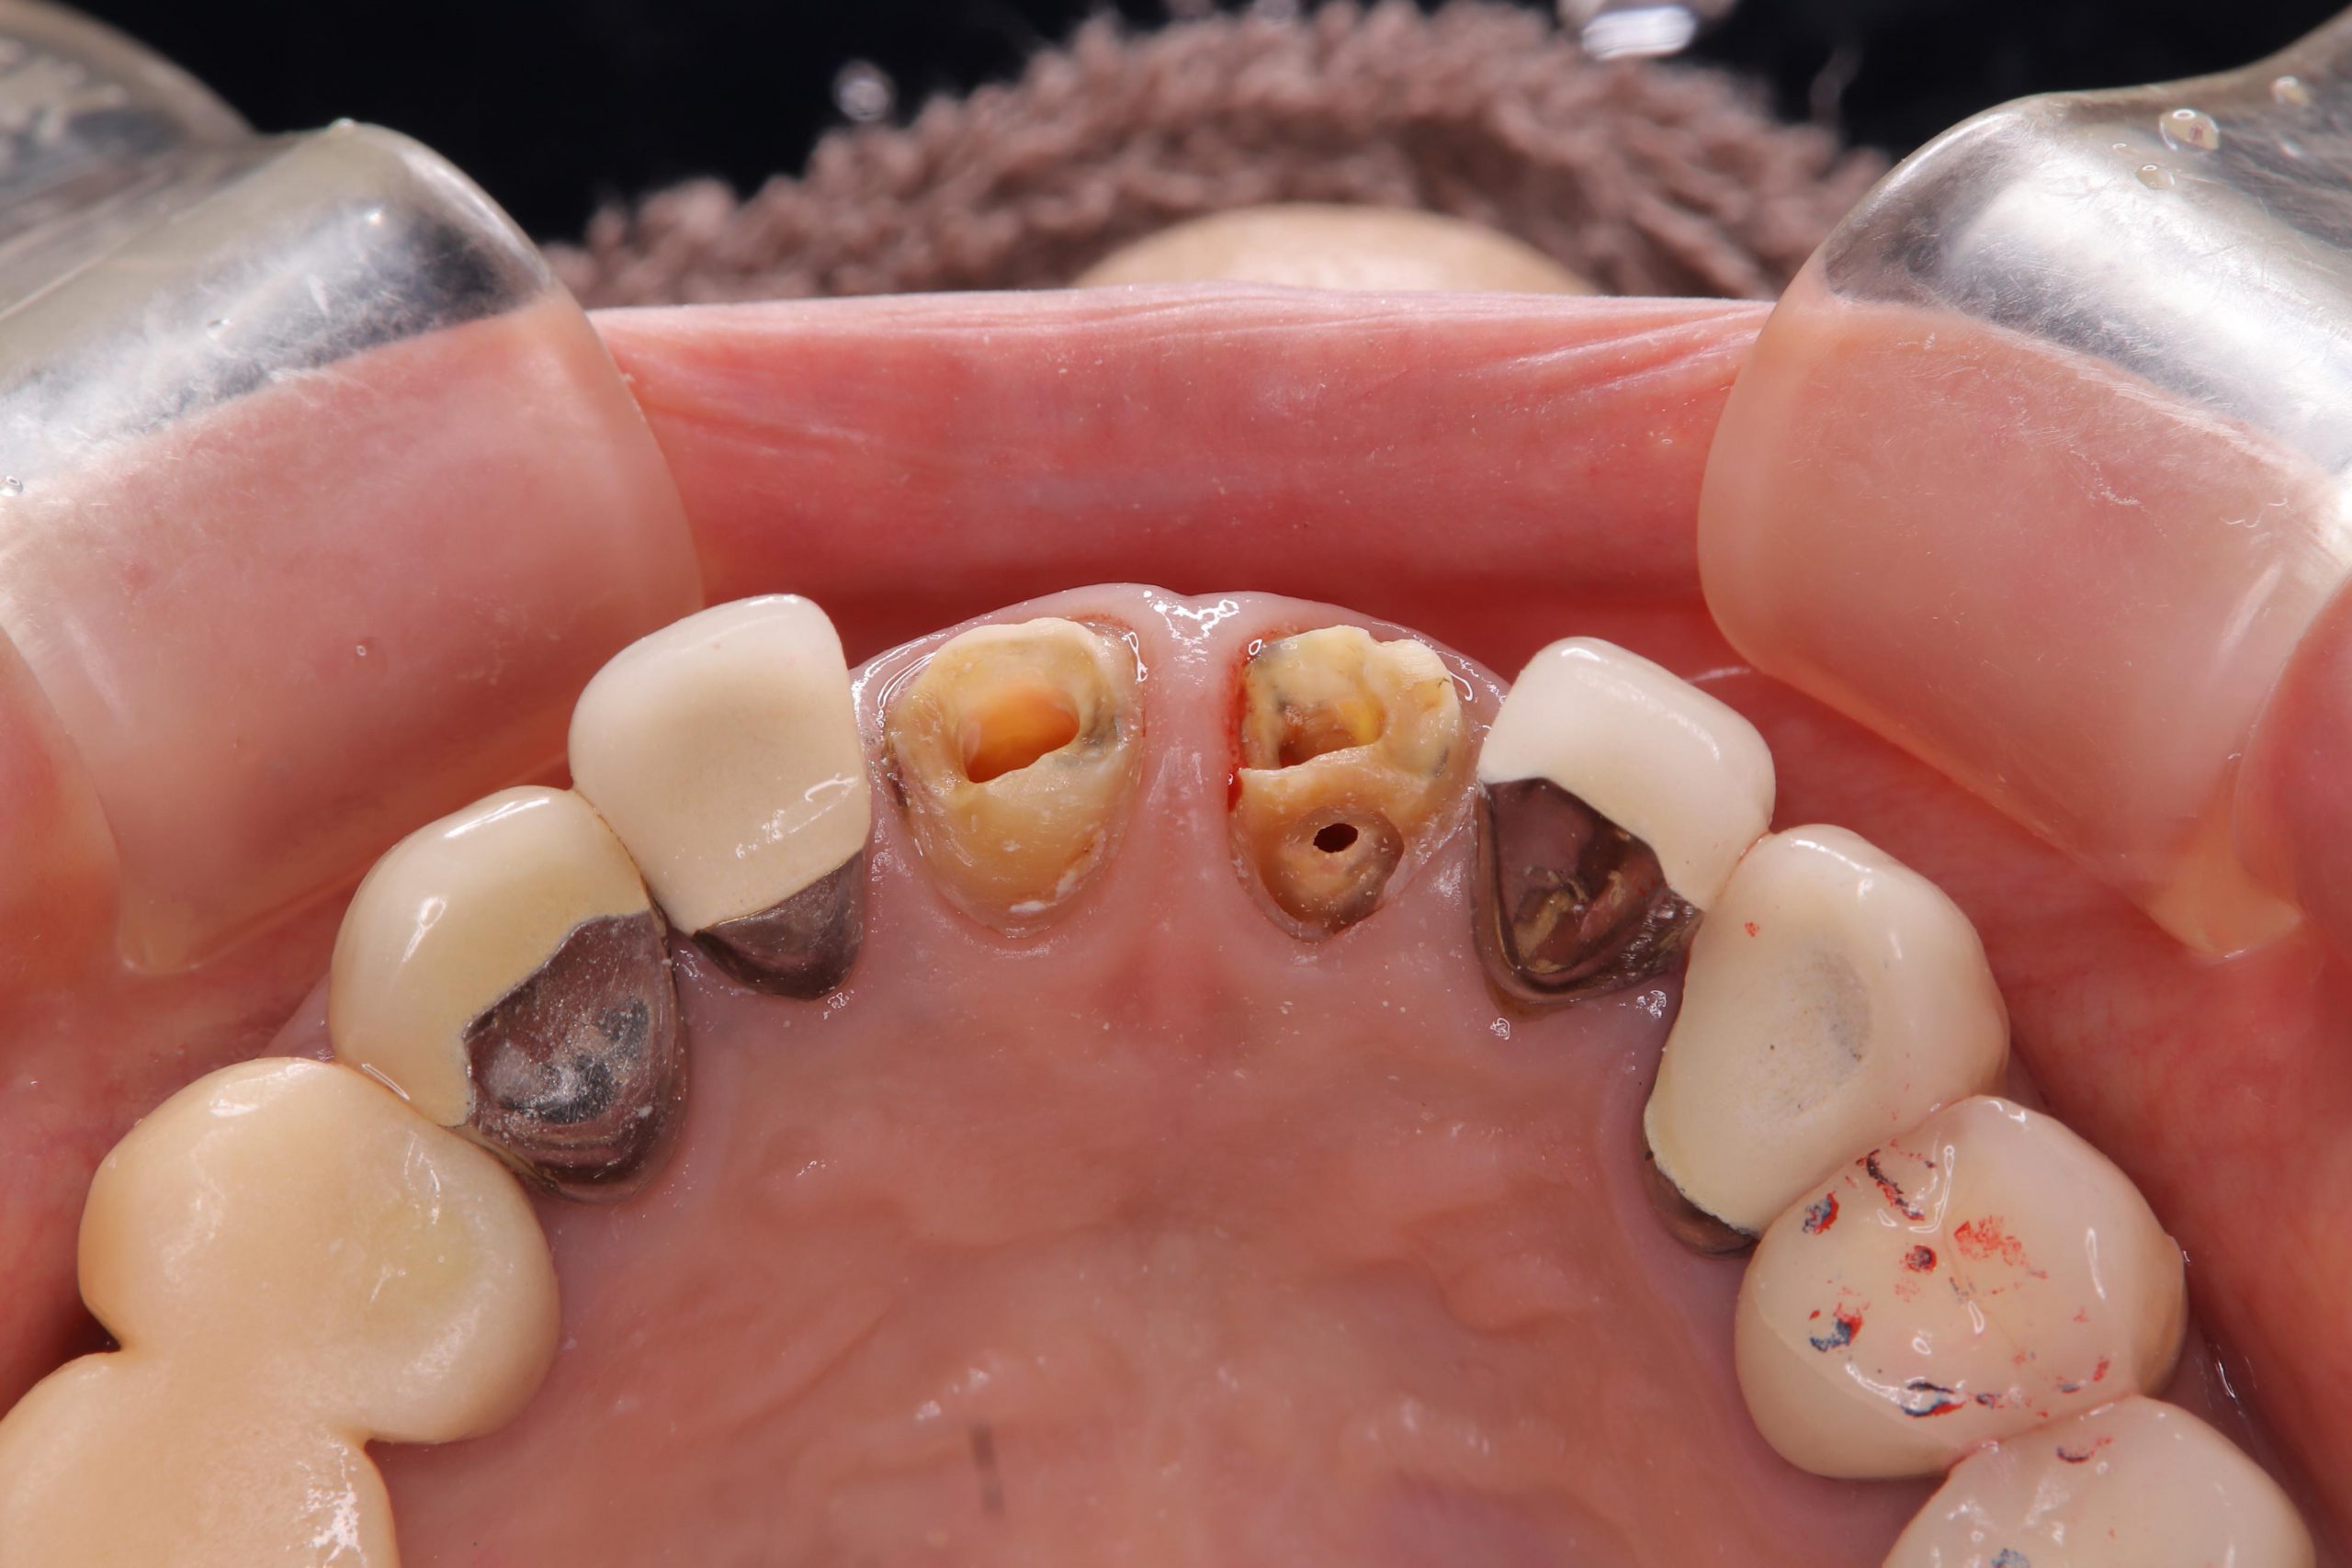

上顎前歯部は、根管治療から行うために、

クラウンやコア(土台)を除去したところ、内部にむし歯が進行している部位もあり、下の写真のような状態でした。

歯質の辺縁が、歯肉から十分に出ていない場合には、治療後に歯の破折やコアの脱離、辺縁からの感染等を起こすリスクが高くなるので、矯正で歯を引き出したり、外科的に歯肉の位置を変えたりして対処します。

今回は、そのような対応は必要ないと判断し、再根管治療を行い、ファイバーコアによる築造(土台作製)を行いました。